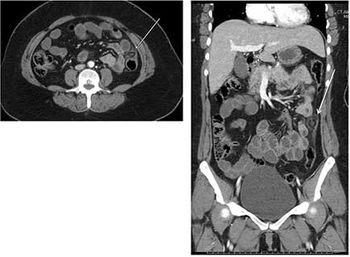

Clinical History: A 42-year-old woman with no significant past medical history presented with three days of sharp left sided abdominal pain with associated nausea and anorexia.

Published: February 19th 2014 | Updated: